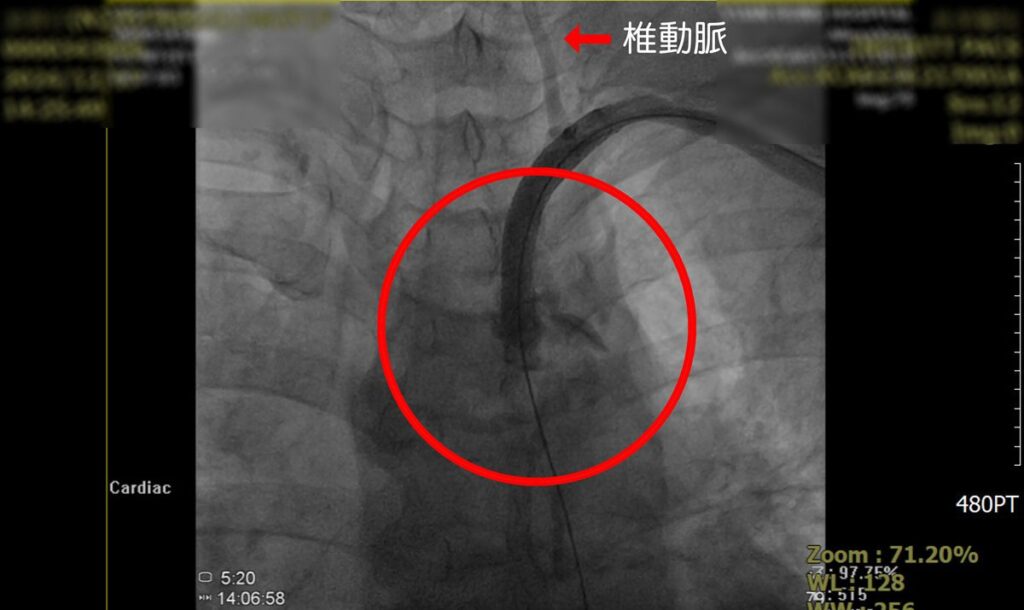

賴主任說,馬上推測患者本身動脈存在嚴重狹窄,導致洗腎的血流偏低,當下安排血管攝影,看到患者鎖骨下動脈開口處幾乎完全阻塞,這種情況稱為「鎖骨下動脈竊血症候群」。

▲賴主任說,馬上推測患者本身動脈存在嚴重狹窄,導致洗腎的血流偏低,當下安排血管攝影,看到患者鎖骨下動脈開口處幾乎完全阻塞,這種情況稱為「鎖骨下動脈竊血症候群」。(圖/員榮提供)